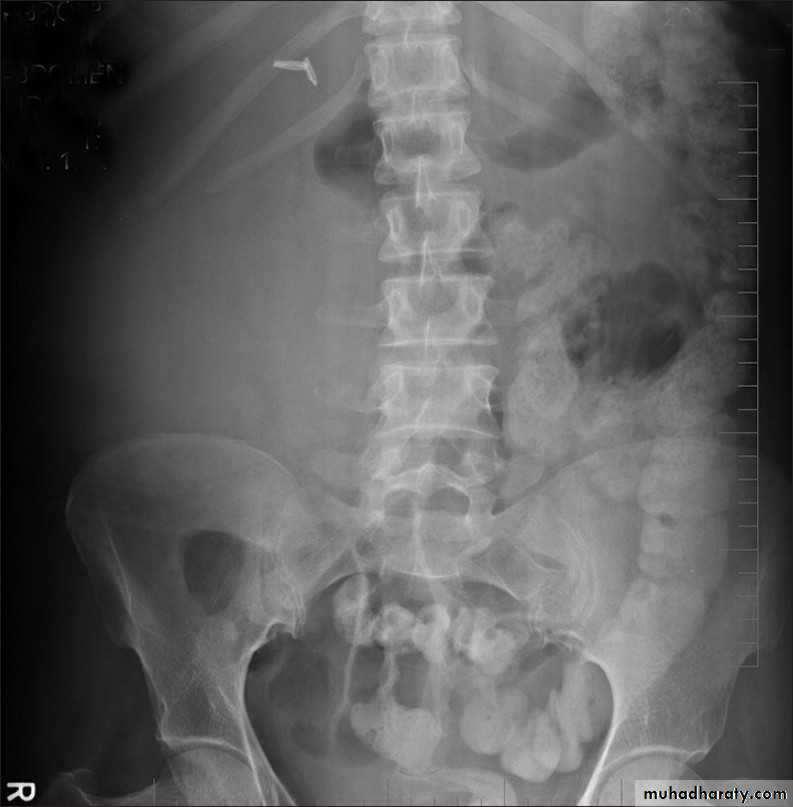

Ureteric calculi (stones):

-Over 90% of calculi are radiopaque on plain films and virtually all on CT as very sensitive for detection of calculi, even those that appear radiolucent on plain film.-Most of these stones are a mixture of calcium oxalate and phosphate.

-Only pure uric acid and xanthine stones are radiolucent on plain x-ray but CAN be identified by CT or US, uric acid stones are associated with increased uric acid excretion in urine as in gout.

Now CT scans used during acute renal stone-Non contrast CT sensitively identify calculi and non opacified collecting system down to the level of obstruction. it has a sensitivity of 97% and specificity of 96% for detection of ureteral calculi

• Ddgx of stone on KUB :

• 1. Gall stone• 2. calfied LN , cartilage ,fibroid,

• 3. Phlebolith: round, lucent centre.